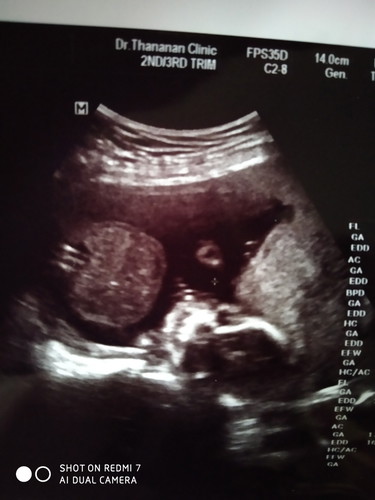

ใครรู้บ้างค่ะในภาพอัลตร้าซาวด์เด็กอยู่ตรงไหน ในวงกลม หรือ นอกวงกลม?

ดูไม่ออกเลยค่ะแม่ รูปนี้6เดือนค่ะ กลมๆศีษะน้องค่ะ